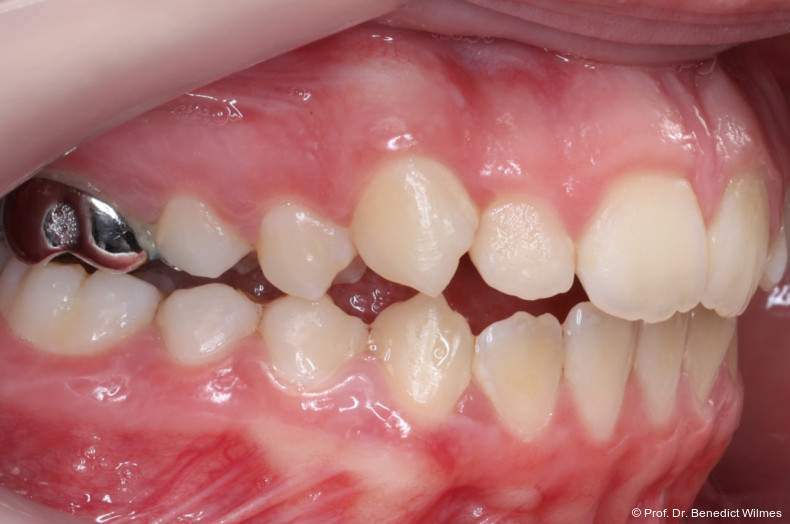

Eine 13-jährige Patientin stellte sich mit beidseitigem Kreuzbiss, einem anterioren offenen Biss und einer Angle Klasse II vor. Das viszerale Schluckmuster wurde mittels logopädischer Maßnahmen umgestellt, der offene Biss persistierte jedoch (Abb. 3a–l).

Behandlungsalternative

Als alternative Therapie wurde die chirurgische Korrektur des offenen Bisses nach Abschluss des Wachstums vorgeschlagen. Eltern und Patientin entschieden sich allerdings für die non­chirurgische und weniger invasive Molarenintrusion.